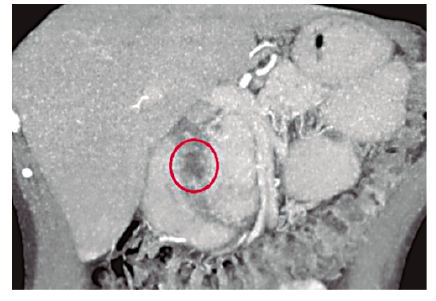

En la TCMD de abdomen con contraste endovenoso se observan imágenes quísticas parietales (Figura 2) y engrosamiento de la pared duodenal con estrechamiento de su luz (Figura 3). Además se logra visualizar a nivel del surco pancreaticoduodenal rarefacción de la grasa y dilatación del colédoco (Figuras 4 y 5).

Afecta predominantemente a varones entre 40 y 50 años con historia de abuso de alcohol, aunque su etiología es incierta.3 El diagnóstico representa un desafío para el médico radiólogo, que frente a una masa de morfología laminar entre la cabeza pancreática y la segunda porción duodenal, que se presenta en la TCMD como una formación hipodensa (Figura 4) acompañada de engrosamiento concéntrico de la pared duodenal con estenosis de su luz,4 y presencia de formaciones quísticas en la pared del mismo.5 (Figuras 2 y 3), debe reconocer los múltiples diagnósticos diferenciales, como el carcinoma ductal pancreático y el carcinoma duodenal.